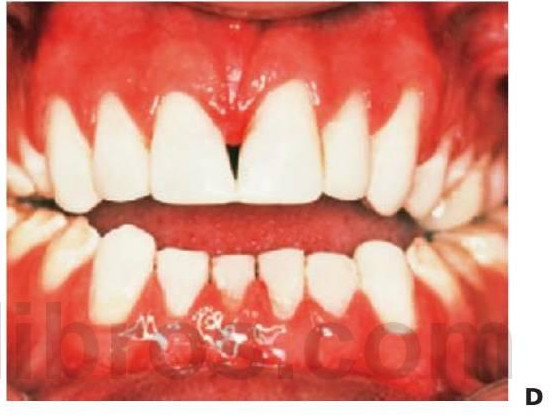

- Varios dientes ausentes (fig. 9.1 B).

Los dientes son pequeños y cónicos y a menudo presentan un gran diastema anterior (fig. 9.3). Sus manifestaciones pueden limitarse a un solo diente ausente o a un incisivo lateral en clavija (v. hipótesis de Lyon, más adelante) y las mujeres heterocigóticas suelen ser diagnosticadas gracias a este tipo de dentición.

Dentro del grupo de displasias ectodérmicas, se observan asimismo modos de herencia autosómica tanto dominante como recesiva. Si se compara con la displasia ectodérmica hipohidrótica ligada al cromosoma X, en las familias con este trastorno no existen diferencias tan acentuadas en cuanto al grado de trastorno entre los hombres y las mujeres (figs. 9.2A, 9.4). Se han identificado mutaciones en el gen MSX1 (4p16.1) en familias con terceros molares y segundos premolares ausentes con o sin paladar hendido/labio leporino, así como en familias con el síndrome diente-uña (Witkop). Se han observado mutaciones del gen PAX9 (14q12-q13) en otras familias con dientes ausentes de forma autosómica dominante.